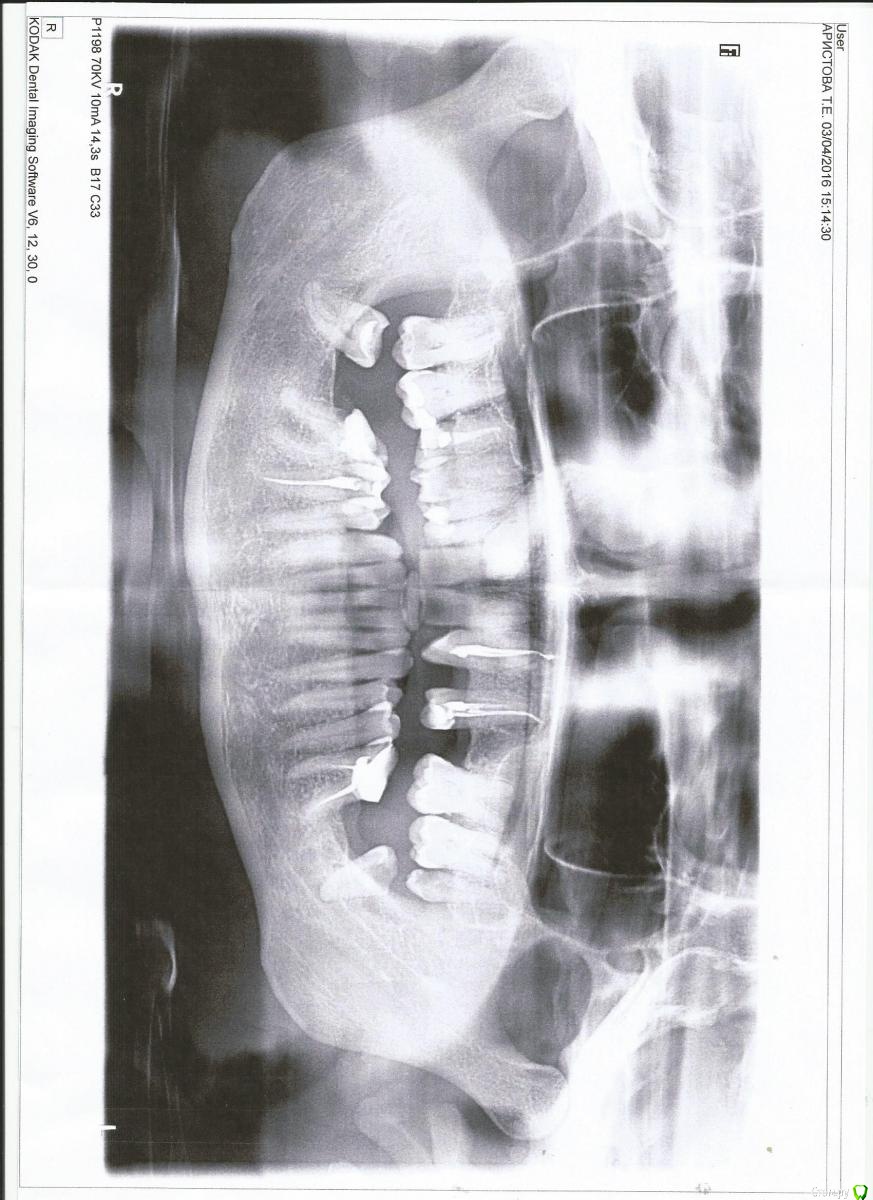

Бинки Опубликовано 22 апреля, 2016 Поделиться Опубликовано 22 апреля, 2016 Здравствуйте, посмотрите, пожалуйста опг, какие варианты протезирования подойдут? Врач ортопед советует на верхней челюсти сделать два моста от центральных резцов в право и лево с депульпированием всех хороших зубов под коронки. Еще предлагают внизу справа сделать мост от 8 до 5 го зуба с протезированием седьмого и вкладкой в шестой. Жалко здоровые зубы, над одним депульпированным клыком после анестезии уже месяц как образовалась шишка, сначала была болезненная теперь почти не беспокоит. Второй клык ретинирован вместо него два молочных зубика, страшные черные, но не удалены и держатся на пломбах. Мне 40 лет. Ссылка на комментарий

red_butler Опубликовано 22 апреля, 2016 Поделиться Опубликовано 22 апреля, 2016 Удалить все зубы мудрости и 4.6. По возможности перелечить 1.5 2.3 2.5 3.6Консультация ортодонта. Имплантация и протезирование. Ссылка на комментарий

red_butler Опубликовано 22 апреля, 2016 Поделиться Опубликовано 22 апреля, 2016 Можно ли поподробнее описать что конкретно удалить Удалить все зубы мудрости и 4.6. на верху слева два импланта, и на нижней челюсти в позиции седьмых зубов.Протезировать 1.5 2.3 2.5 4.5 и если объем твердых тканей позволяет то и 3.6Покажите фото зубов, по ОПГ не понял есть ли молочный зуб, или ретенированный зуб - сверхкомплектный. Ссылка на комментарий

Бинки Опубликовано 22 апреля, 2016 Автор Поделиться Опубликовано 22 апреля, 2016 фото зубов смогу сделать по-позже, сейчас на работе. Ретинированный зуб не сверхкомплектный, знаю это еще с 15 лет, тогда врачи приняли решение ничего с ним не делать, оставить молочную двойку и тройку. Двоек коренных не было зачатков вообще.Слева:Когда молочная двойка вылетела, носила пластинку с зубом и на ее месте вылез клык криво, а потом молочный клык развалился и выпал. Справа остались молочные, а коренной так и остался в десне. То что советует мне ортопед: два мостовидных протеза на верх это нормально? Ссылка на комментарий